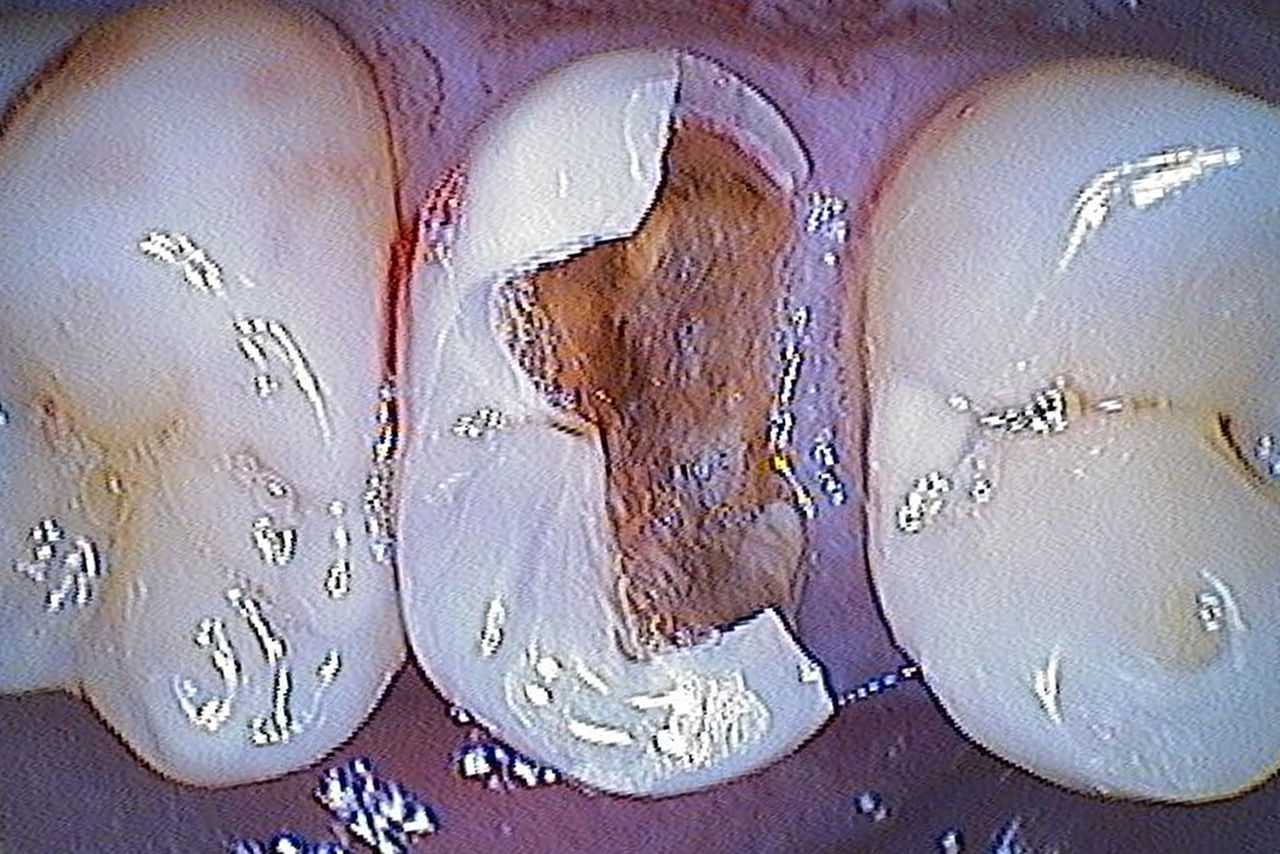

Before: Large insufficiency of the composite filling on tooth 16 with distal marginal ridge cracks, a lingual wall crack and distal recurrent decay.

After: Highly aesthetic full-surface glass-ceramic crown.